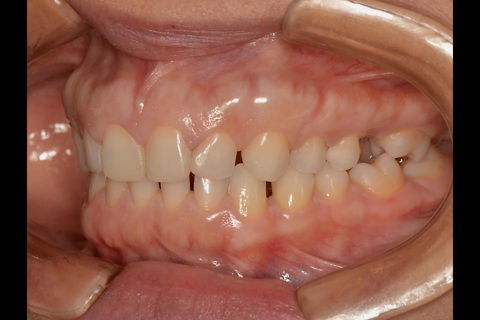

Fotos do caso